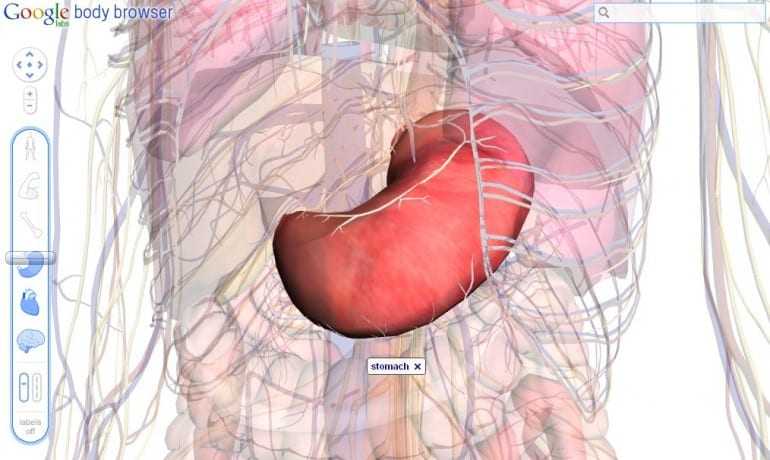

Αν και ακόμη σε πειραματικό στάδιο το Body Browser επιτρέπει σε χρήστες να ‘τεμαχίζουν’ το ανθρώπινο σώμα μέσα από τις στρώσεις του σώματος σε ένα τρισδιάστατο μοντέλο. Με χρήση εικονικών ‘μαχαιριών’ γίνεται εύκολα η εξερεύνηση των οργάνων που μας κάνουν να… λειτουργούμε.

Στήθηκε για να είναι και μια επίδειξη της τεχνολογίας WebGL, επιτρέπει σε έναν browser να σχηματίζει 3D γραφικά χωρίς να υπάρχει ανάγκη για plugins. Το Body Browser για την ώρα είναι δουλειά που στήνεται στα Google Labs και όποιος έχει έναν WebGL-enabled browser – όπως οι τελευταίες εκδόσεις των Chrome και Firefox για Windows και ο Safari για Mac – θα πρέπει να μπορούνε να ‘εισέλθουν’ σε πολλαπλές στρώσεις, να κάνουν zoom in και out, και να αναζητούν συγκεκριμένα μέρη του σώματος όπως κάνουμε για τις πόλεις του Google Maps.

Είναι μια εντυπωσιακή επίδειξη της HTML5 και WebGL τεχνολογίας και πραγματικά θα δούμε πολλά ωραία με αυτή αφού έτσι δεν χρειάζεται να χρησιμοποιούνται δυνατές κάρτες γραφικών.